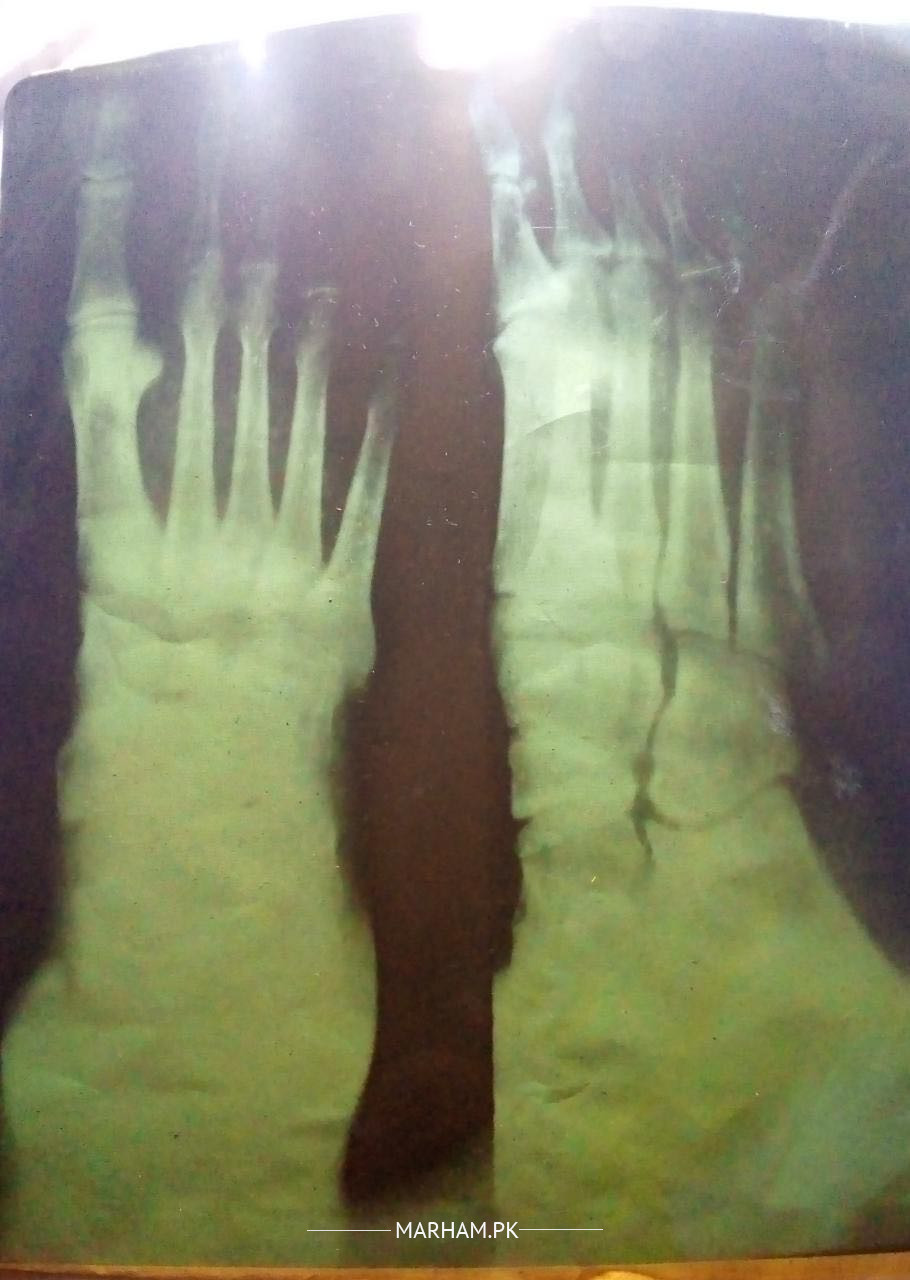

AoA!I am a medical student of Endotech! 10 days ago my uncle got injured due to machine falling. An x-ray is immediately done but according to the doctor no fracture is visible in the x-ray. As I am a bit confused about the x-ray. As Swelling and pain do not get better with the medicine prescribed by the doctor. What should he do now?

xray is low quality...picture of sole of foot needed. Is he able to walk and put weight on it while walking ? for now, rest and using support while walking is recommended.

wsalam xray quality is poor.

repeat good quality xray .

X-rays are of poor quality. Mechanism of injury is concerning for a lisfranc injury. Will suggest to see a specialist and get weight bearing X-rays of foot